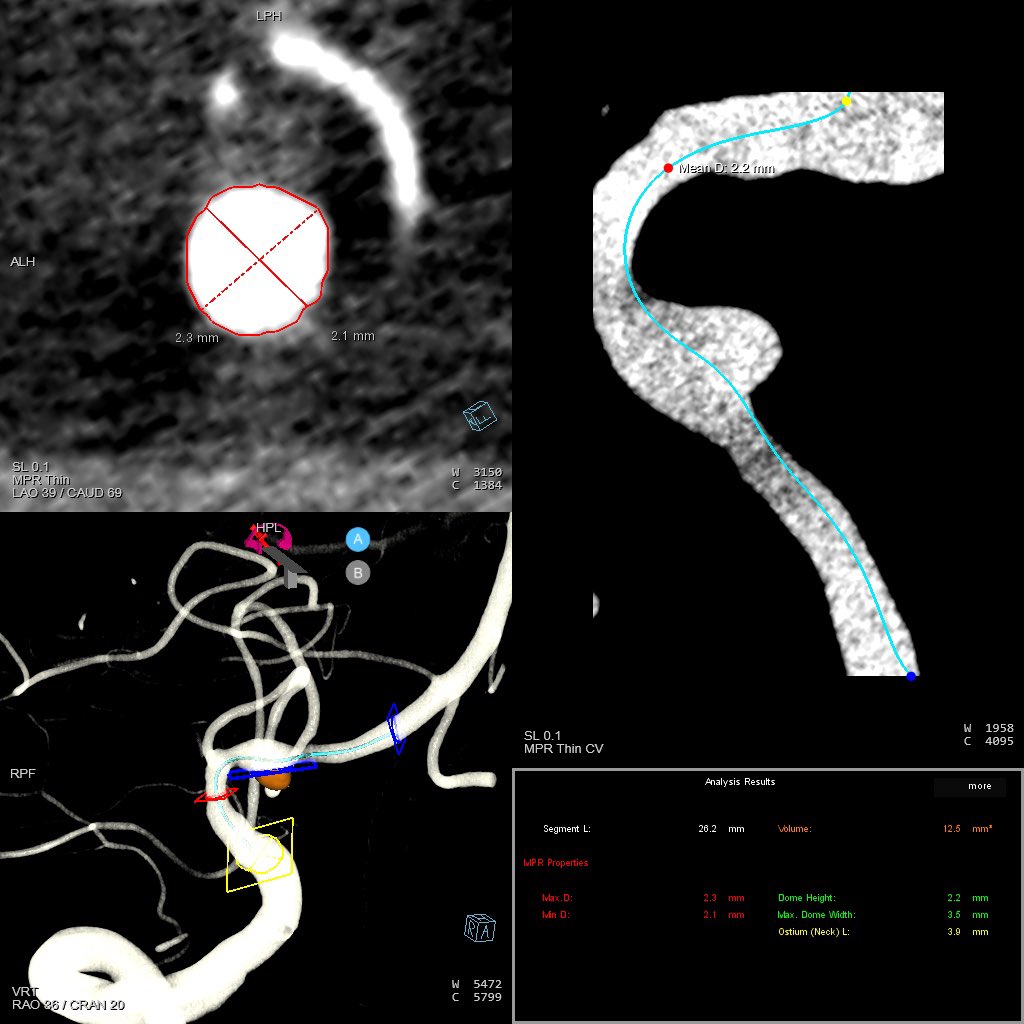

Tumor Workflow: Glomus tympanicum embolization

A case that represents an expansion into a new class of tumor embolization. Planning, imaging, and access from beginning to end.